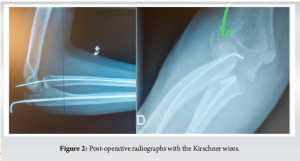

After closed reduction of the dislocation, percutaneous anterograde nailing of the ulna was performed with a 2.5 mm-Kirschner wire, associated with a percutaneous anterograde nailing of the radius with a 1.5 mm-Kirschner wire with temporary arthrodesis of the humero-radial joint (Fig. 2). A 6-week long arm cast was applied. Six weeks later, the cast and the Kirschner wires were removed. Physiotherapy 4 times a week was started associated with a daily 30-min arthromotor (Kinetec) to help restore the range of motion of the elbow and forearm.